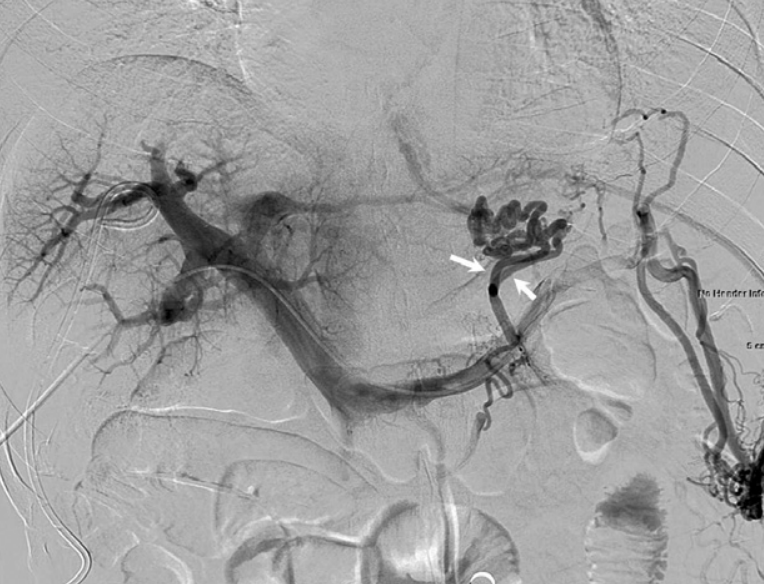

Fig. 2

Splenoportal (A) and left gastric (B) venograms show gastric varices through which the venous blood flow runs from two inflow veins (arrows) of the left gastric vein to distal esophageal varices.